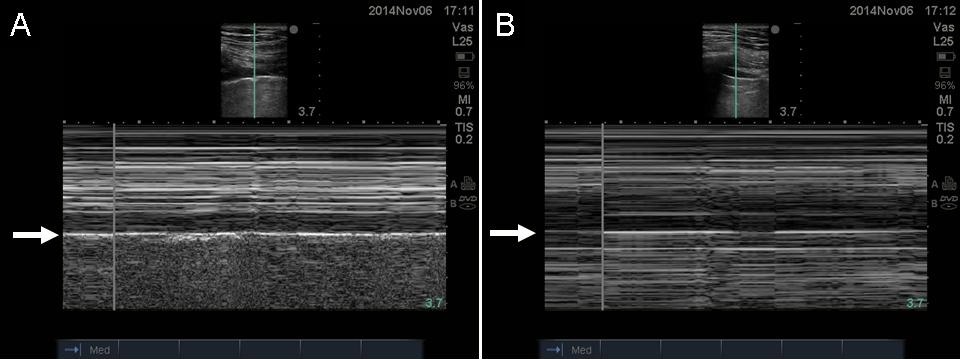

What is the stratosphere/barcode sign on M mode in lung ultrasound?

Classic sign seen with pneumothorax (aka Barcode sign)

Compare and contrast the seashore sign vs. the stratosphere sign?

Stratosphere sign: absence of pleural contact with the lung = the artifact is static thus you see only horizontal lines instead of the sandy beach pattern